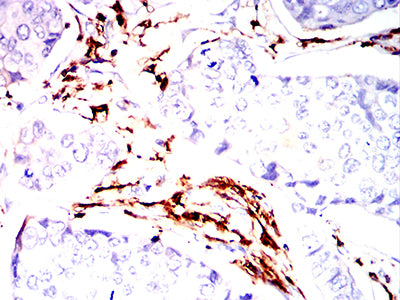

| IHC | 1/50-1/100 | Human,Mouse,Rat |

The MonoMethyl-p53 (Lys370) antibody is widely employed in cancer research to study p53 regulation in tumorigenesis, particularly in cancers with wild-type p53. It enables detection of this modification via techniques like Western blotting, immunohistochemistry, and immunoprecipitation, aiding investigations into p53's functional dynamics in cell lines, tissues, or patient samples. Studies using this antibody have provided insights into how Lys370 methylation affects p53-mediated tumor suppression, its crosstalk with other modifications (e.g., phosphorylation, acetylation), and its potential as a biomarker or therapeutic target. Researchers frequently apply it in models of colorectal, breast, and lung cancers to explore context-specific regulatory mechanisms. Proper validation with methylation-deficient mutants or enzymatic treatments is essential to ensure specificity in experimental settings.